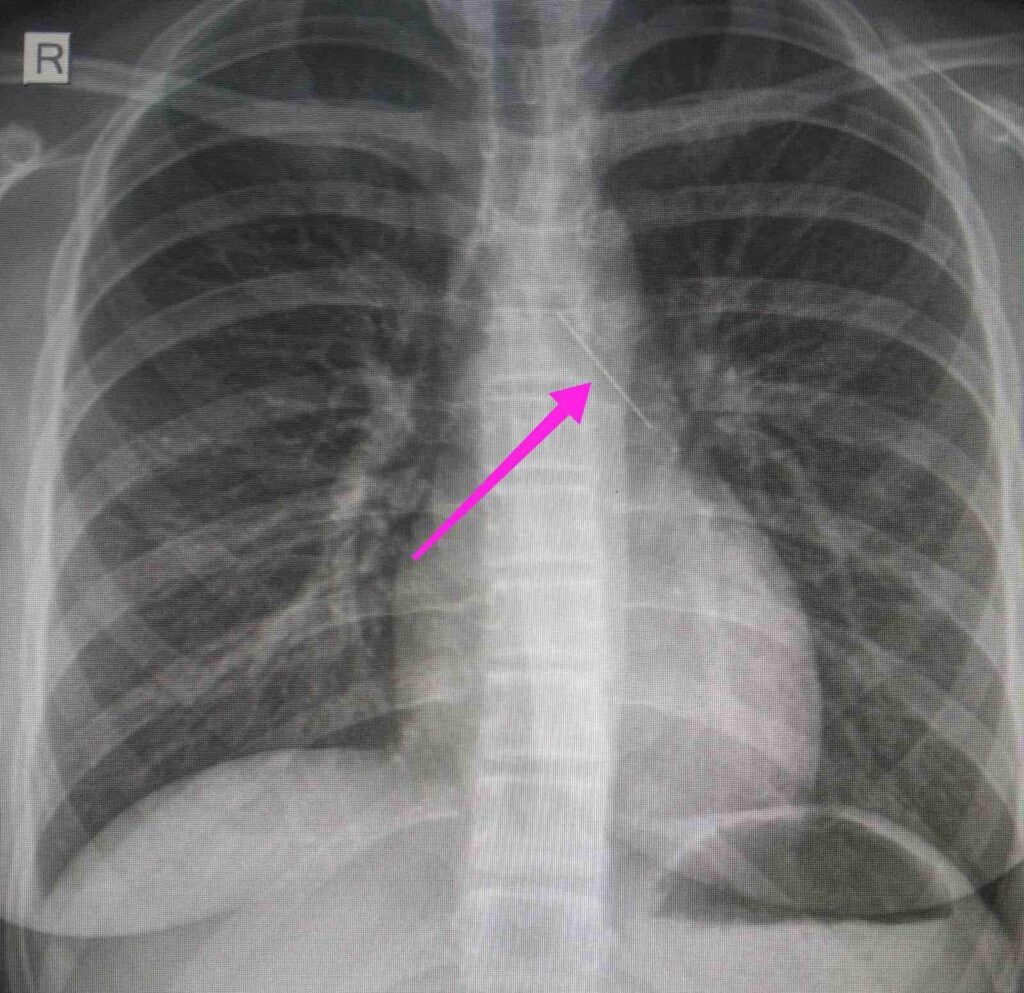

Από την απεικονιστική διερεύνηση που πραγματοποιήθηκε με ακτινογραφία θώρακος αρχικά και ακολούθως με αξονική τομογραφία θώρακος, διαπιστώθηκε η ύπαρξη αιχμηρού μεταλλικού ξένου σώματος στην αναπνευστική οδό (αριστερός κύριος βρόγχος) και όχι στην πεπτική οδό, αναφέρει η ανακοίνωση του νοσοκομείου, στα μέσα κοινωνικής δικτύωσης.

“Χθες 30/1/2022 στις 16:00 στο Τ.Ε.Π. του ΓΝΘ Ιπποκράτειο, προσήλθε ανήλικη συνοδευόμενη από τους γονείς της, μετά από αναφερόμενη κατάποση ξένου σώματος (καρφίτσα). Από την απεικονιστική διερεύνηση που πραγματοποιήθηκε με ακτινογραφία θώρακος αρχικά και ακολούθως με αξονική τομογραφία θώρακος, διαπιστώθηκε η ύπαρξη αιχμηρού μεταλλικού ξένου σώματος στην αναπνευστική οδό (αριστερός κύριος βρόγχος) και όχι στην πεπτική οδό.